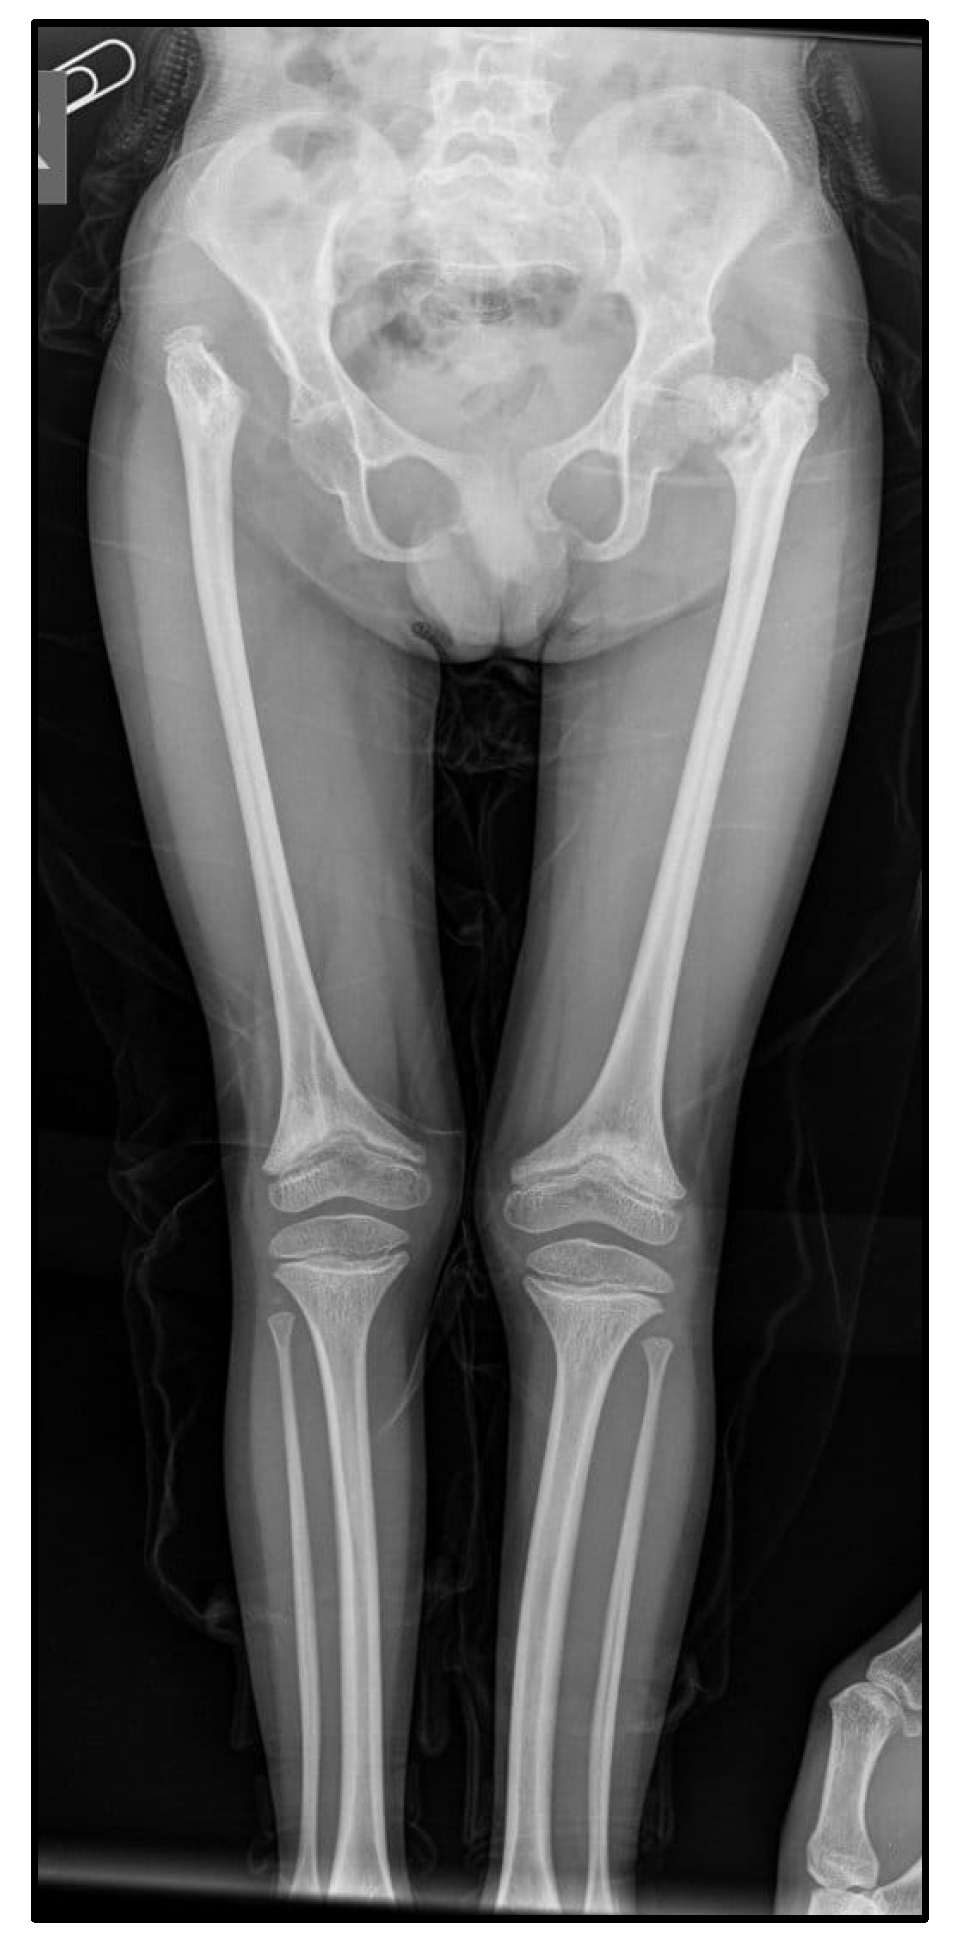

X-Rays

| 2024 | Partial empty sella (October 2024) | Widened, flared “champagne glass” metaphyses with irregular contours in the forearm bones bilaterally. The radial and ulnar diaphyses are curved bilaterally. The left radius is shortened (4.5 cm versus 5.8 cm on the right). Ossification nuclei are present in the hand skeleton: trapezium, trapezoid, capitate, hamate, and lunate. The scaphoid nucleus is very small (~2 mm); the distal radial epiphysis nucleus is rudimentary—bone age of 4–5 years. Flared and irregular metaphyses in the distal phalanges and metacarpals (Figure 3). | The right acetabular cavity is flattened and vertically oriented. The femoral head nucleus on the right is not visible, and the right femur is elevated. The left acetabular cavity is slightly vertically oriented. The left femoral head nucleus is formed but irregular and fragmented. Coxa vara. Bilateral femoral metaphyses are widened, flared, and irregular, with an “inverted V” appearance of the growth line. Bilateral tibial metaphyses are also widened and flared (Figure 4). | Bone age = 4–5 years | |